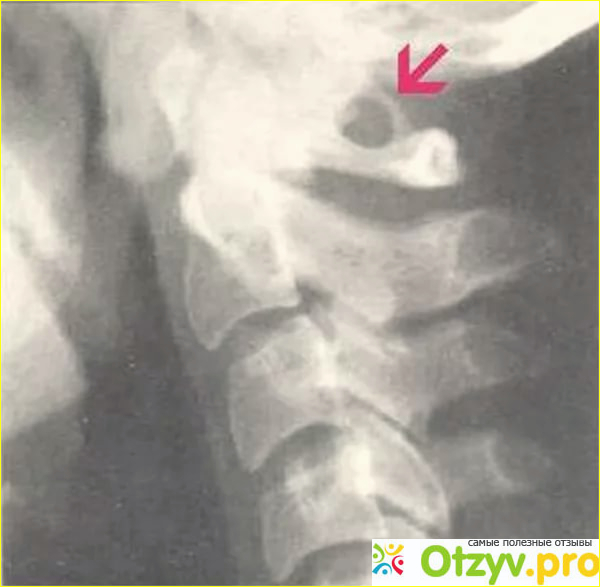

Аномалия киммерли относят к врожденным нарушениям и зачастую лишь УЗИ , МРТ, рентген снимки могут найти источник головокружений и ухудшения самочувствия, уменьшение притока крови к задним отделам мозга. Может наблюдаться с обеих сторон первого шейного позвонка.

Аномалия киммерли на первый взгляд как обычный остеохондроз, также можно испытывать боли при резких поворотах головы, движений.